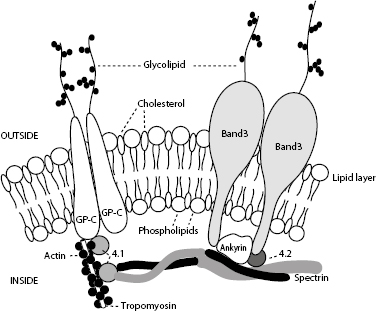

The red cell wall is a typical lipid bilayer, comprising mainly phospholipids and cholesterol (Fig. 1.25). Membrane proteins and glycoproteins are inserted into the lipid bilayer, some in one leaflet only and others spanning the entire membrane. These integral proteins include hormone receptors and enzymes, which usually only partially penetrate into the bilayer, and transmembrane proteins, which include the transport carriers for ions and water-soluble substrates, such as glucose. The transmembrane proteins maintain cation–anion homeostasis within red cells. Abnormalities in ion pumps can result in a shortened red cell lifespan.

The red cell skeleton forms the scaffolding for the lipid bilayer and plays an important role in membrane stability and deformability. Deformability is the most important property of RBCs required for normal survival, particularly as cells traverse capillary beds and the exacting environment of the spleen. Interactions between skeletal proteins, such as spectrin, ankyrin, and actin, and the lipid bilayer maintain membrane shape, flexibility, and durability. The organization of membrane phospholipids is also stabilized, and cell-surface activities (e.g. anion and glucose transport) are influenced by interactions between skeletal proteins and transmembrane proteins. Skeletal proteins link to the lipid membrane via two main interactions: spectrin–ankyrin band 3 and spectrin–actin band 4.1. The bands are named according to their migration patterns on electrophoresis. Many are now assigned names that reflect their function, for example, band 3 is now known as AE1 for its role as an anion exchange protein or channel.